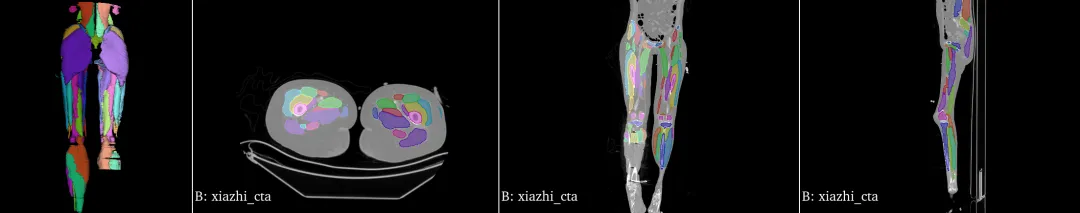

下肢肌肉分割:

下肢数据超大,分割时间超久。有只小腿分割效果差些